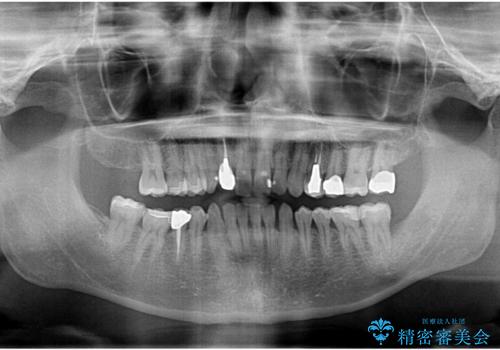

- 83.6万円(仮歯・emaxインレー×8・ジルコニアクラウン×2)費用は治療当時の料金となります

見た目の改善だけではなく、長期的に虫歯の再発を防ぎ自分の歯を守るために銀歯をはずし、セラミック修復物・補綴物による機能回復を行いました。